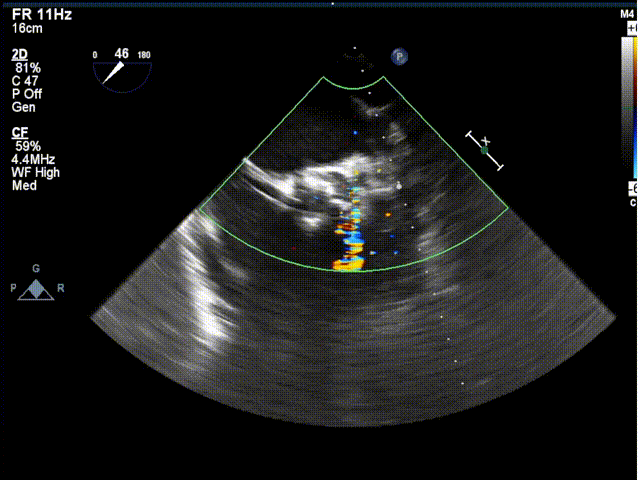

术中超声

超声结果示:无明显瓣周漏,主动脉瓣口峰值流速为1.99 m/s,峰值跨瓣压差为 16 mmHg。